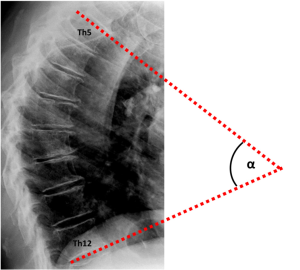

During the periodical research center visits, radiographic examinations of the spine were obtained using a digitized Fuji Computed Radiography system (FUJIFILM Medical Systems). All radiographs were acquired digitally according to a standardized protocol, with a focus to detector distance of 120 cm. A team of trained research assistants processed lateral spine radiographs (vertebral levels Th4-L4) with SpineAnalyzer® software (Optasia Medical Ltd, Cheadle, UK) (18). SpineAnalyzer® software can automatically identify vertebral body margins on digital radiography, determine the exact heights of the vertebrae, and calculate the shape and degree of height reduction. After labeling the vertebrae of interest by placing thirteen points at the center of each vertebral body from Th4 to L4, the software will automatically outline each labeled vertebra with six morphometry points, corresponding to the four corners of the vertebral body, as well as the mid-point of the superior and inferior endplate. The analyst can make manual adjustments to these six morphometry points to fine-tune their exact locations for accurate measurements, and thereafter, the pixel coordinates of these points are saved. We extracted the raw coordinate data of the two upper corners of Th5 and the two lower corners of Th12 to calculate the Cobb’s kyphosis angle. For comparison, two readers (A.A.M. and S.S.) performed independent manual measurements of the Cobb’s kyphosis angle between Th5 and Th12 (Figure 1) for a sample of n=99, which had vertebral wedging at a minimum of three levels and presence of vertebral body endplate irregularities, as described previously (19). The analyses presented in this report concern the sample of n=99 subjects analyzed with both SpineAnalyzer® and the manual measurements of the Cobb’s kyphosis angle between Th5 and Th12.